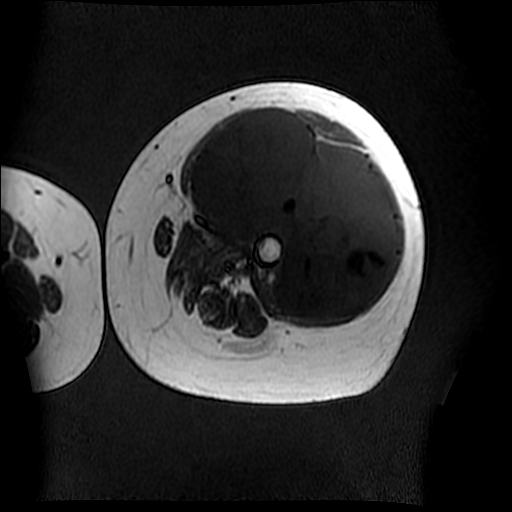

左侧大腿外伤10余年,当时情况不清,发现左侧大腿肿胀7年余,而后又有多次外伤史,近1年来出现疼痛,减重半年。查体:左侧大腿肿胀明显,皮温、肤色正常。

软组织肿块,股骨破坏,增强不均匀强化-----支持恶性肿瘤